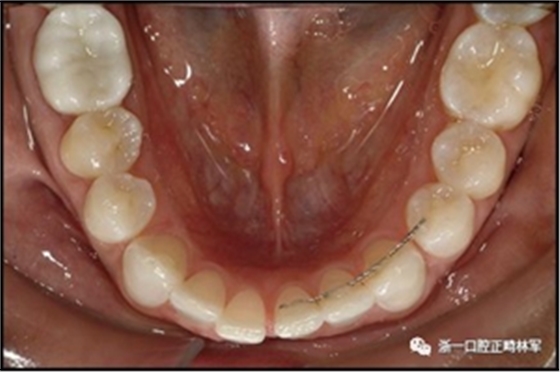

一顆或兩顆尖牙位置的橫向變化可能發(fā)生在與每顆牙齒粘合的小弓絲上,并且在極軟弓絲(圖3)和柔性螺旋弓絲(圖4)上都可以看到。較大直徑的弓絲會(huì)產(chǎn)生不同類型的橫向變化。較硬的弓絲與更小的弓絲相比,在尖牙之間產(chǎn)生更多的相關(guān)關(guān)系。弓絲的扭曲會(huì)導(dǎo)致尖牙的往復(fù)運(yùn)動(dòng)和弓形的歪斜(圖5)。相對(duì)較硬弓絲的向下偏斜可以通過(guò)尖牙產(chǎn)生擴(kuò)張(圖6)。

圖3.極軟弓絲完全完好,在多個(gè)空間平面上的拱形歪斜,右側(cè)尖牙的面部?jī)A斜以及右側(cè)側(cè)切牙和中切牙在相反方向上的扭矩:A,頰面視圖; B,咬合面視圖。